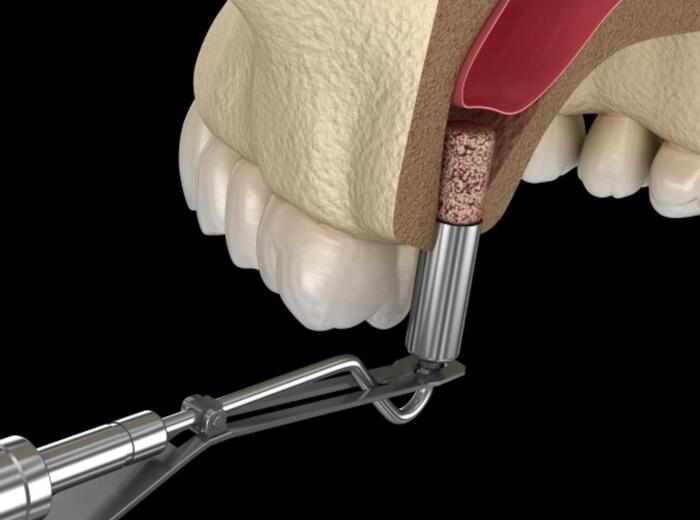

1. Nâng xoang kín

Nâng xoang kín là một kĩ thuật nâng xoang từ bên trong ít xâm lấn, thông qua vị trí đặt trụ Implant và không cần phẫu thuật nhiều lần. Nâng xoang kín thường áp dụng khi mất răng hàm trên, xương hàm trên còn tương đối đủ độ dày (6 – 8mm trở lên) và màng xoang còn nguyên vẹn, không hạ quá thấp, không cần bổ sung xương nhiều.

Tuy nhiên, xoang hàm phải đảm bảo: đáy xoang không gồ ghề, xơ dính, màng xoang không quá dày, không dị tật, không có dịch hay bị viêm.

Quy trình nâng xoang kín được thực hiện theo các bước sau:

- Bước 2: Tạo đường nhỏ dưới chân răng

Bác sĩ gây tê tại vùng cần cấy Implant. Sau đó, tạo đường nhỏ khoảng 3.6mm để các dụng cụ y tế chuyên dụng tiếp xúc được đáy xoang.

- Bước 3: Nâng xoang – ghép xương

Bác sĩ dùng ống đẩy chuyên dụng để nâng xoang hàm lên trên cao. Sau đó, xương cần ghép sẽ được bơm vào lấp đầy khoảng trống đến khi đủ lượng xương yêu cầu.

- Bước 4: Đặt trụ Implant và khâu vạt nướu

Nếu đủ điều kiện phù hợp, trụ Implant sẽ được cấy ngay vào giai đoạn này để tích hợp với xương được ghép. Bác sĩ sẽ khâu vạt nướu bằng chỉ tự tiêu và hướng dẫn khách hàng chăm sóc.